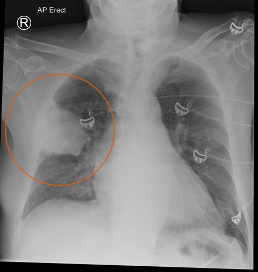

What does this CXR indicate? - Pneumoperitoneum - Pneumothorax - Pulmonary oedema - Consolidation - Pleural effusion

What does this CXR indicate? - Pneumoperitoneum - **Pneumothorax** - Pulmonary oedema - Consolidation - Pleural effusion